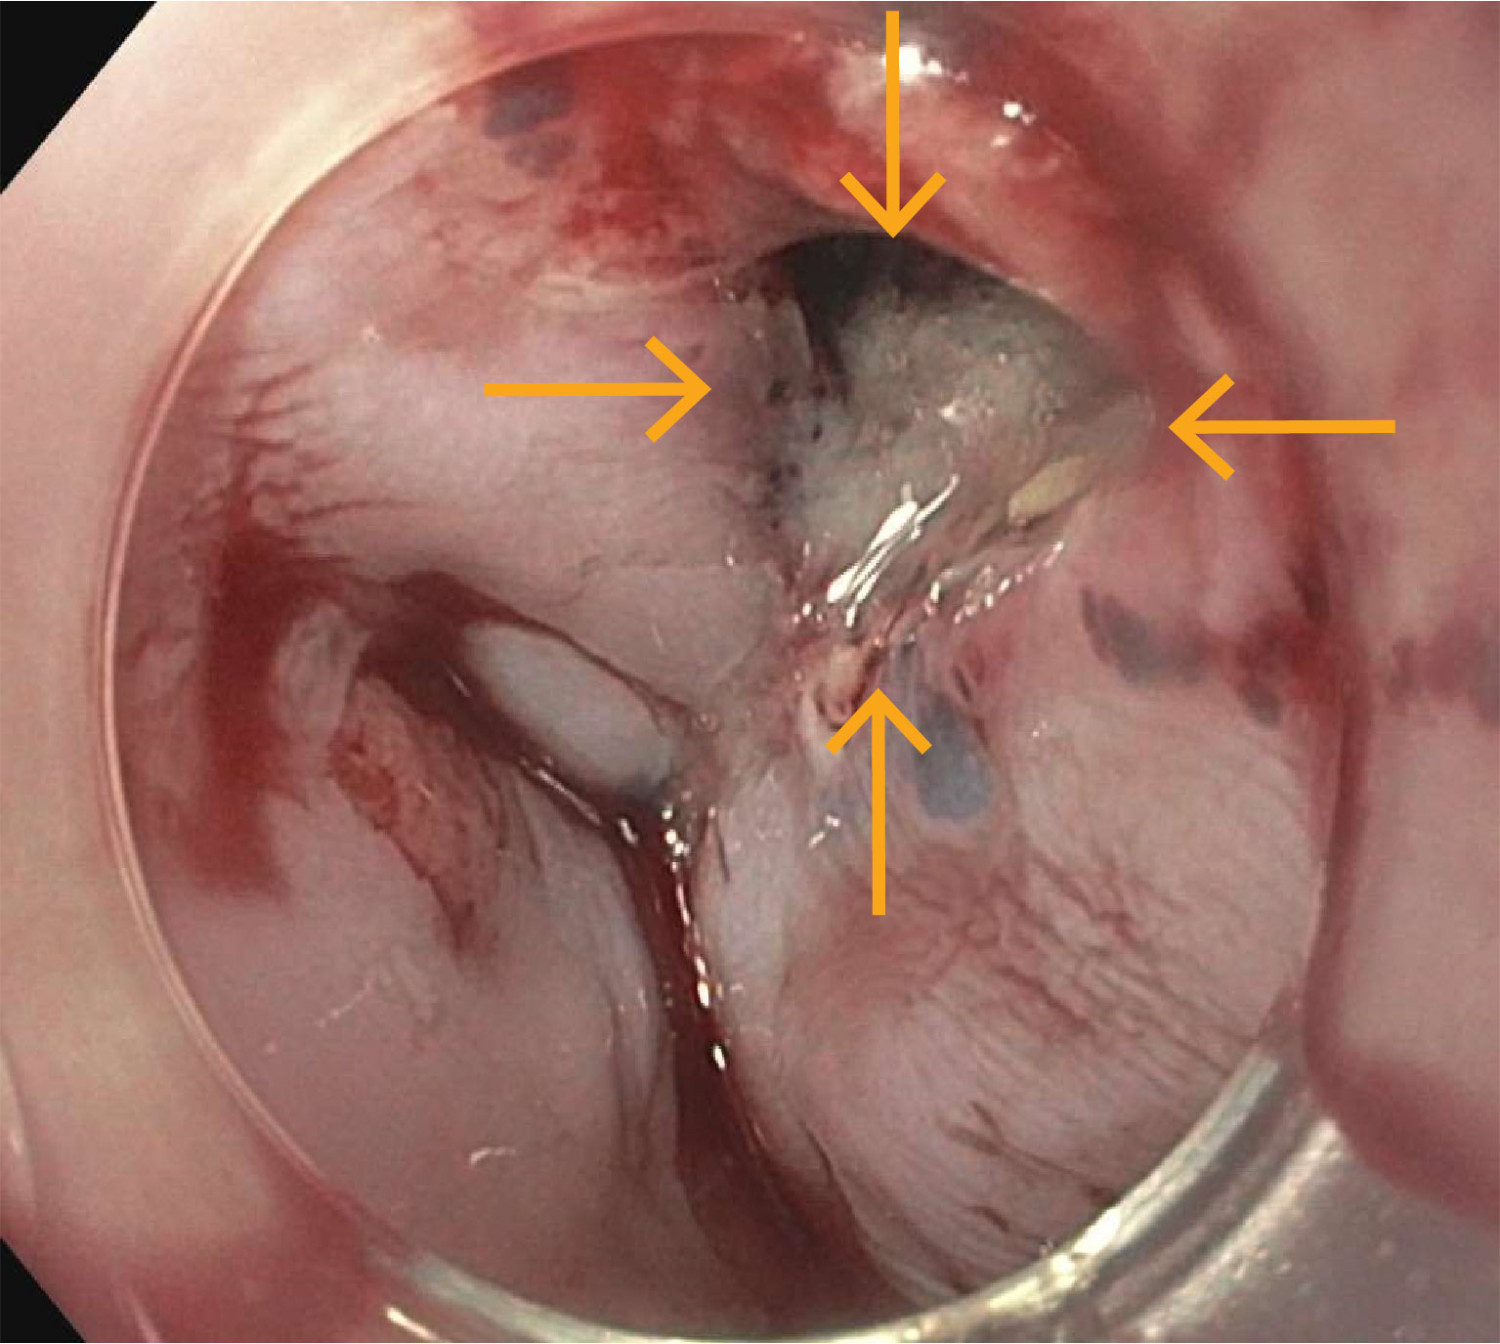

Samlet ga funnene mistanke om ruptur av distale øsofagus, og hun ble samme dag overflyttet til universitetssykehus, der det ble gjort gastroskopi. Denne viste en vel 5 mm stor ikke-blødende perforasjon i øsofagus omtrent 40 cm fra tannrekken (figur 2). Perforasjonen ble behandlet med stent. Det ble ikke sett patologi i ventrikkel eller duodenum.